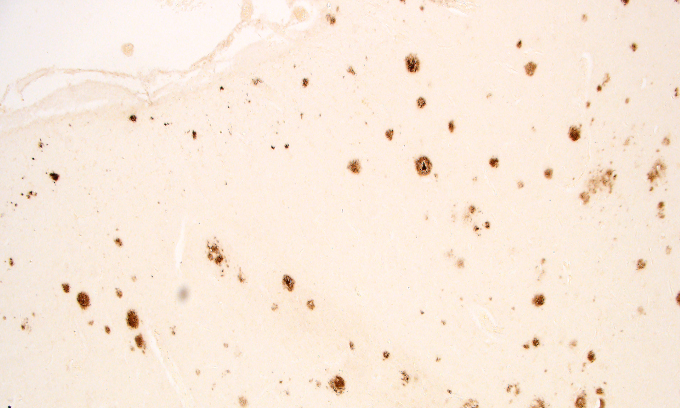

Microscope image of amyloid plaques in brain tissue. The study showed the severity of sleep apnea was linked with a corresponding build-up of amyloid plaques (seen here as brown patches in the brain tissue).

Significantly, the severity of sleep apnea was linked with a corresponding build-up of amyloid plaques.

While the study found both plaques and tangles in the brains of people with sleep apnea, the plaques showed a stronger association with severe sleep apnea.

“In cases of mild sleep apnea, we could only find plaques and tangles in the cortical area near the hippocampus, precisely where they are first found in Alzheimer’s disease,” said Robinson, a researcher in RMIT’s School of Health and Biomedical Sciences and Austin Health’s Institute for Breathing and Sleep (IBAS).